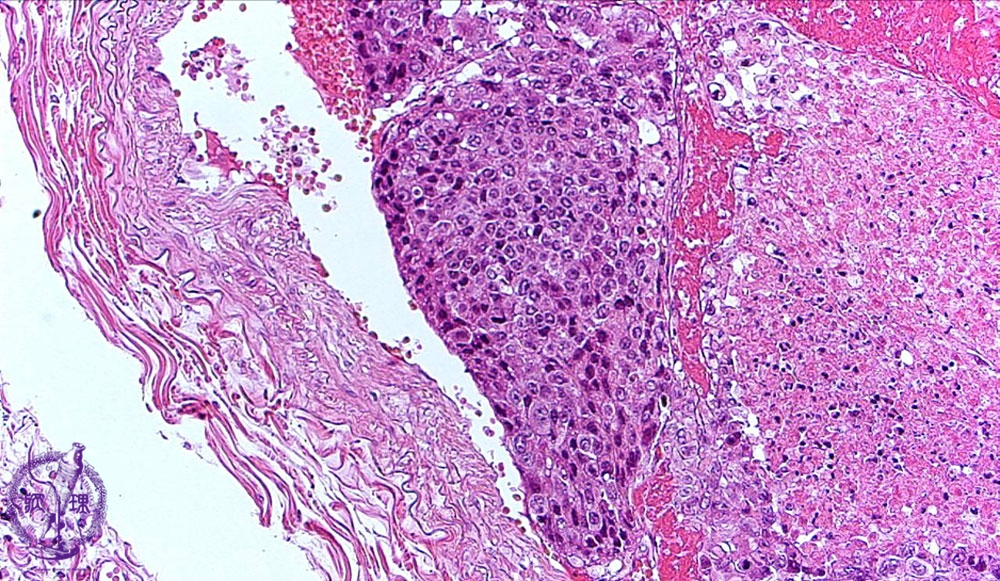

転移性肺腫瘍ミクロ像(HE中拡大)

ミクロ像(HE中拡大):充実性に増生する低分化肝細胞癌が腫瘍塞栓を形成している。腫瘍の右側には壊死が見られる。他の部位では分化度の高い肝細胞癌が見られた。